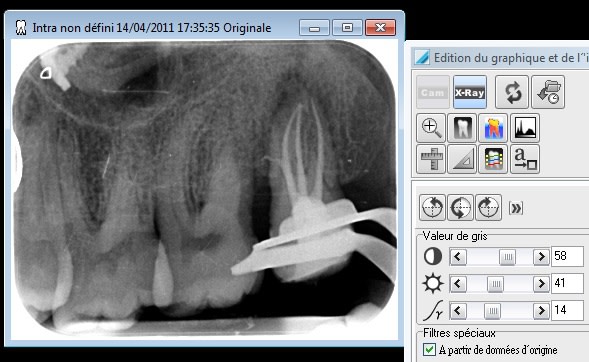

franchement les endos le soir c'est dur!!!!

mais celle ci elle me donne le sourire pour la soirée

Super le canal latéral en mésial, de bonne taille en plus ! comment tu as obturé ?

Le patient peut te remercier...il ouvrait grand j'espère. Même avec la digue, pas évident l'accès.

Comme le dit Marc, c'est surtout pour me défouler après avoir bien galéré que je poste la radio :)

Elle ouvrait carrément pas, en tout cas pas assez à mon goût ! :)

Séquence : Endo Express + Hero shapper et thermafill

Pour tout ceux qui veulent extraire... faut pas déconner non plus, vous voyez rien de la couronne clinique avec le clamp...et il y a une 48... Celle ci aura surement droit à un onlay ... elle est pas si délabrée que ça....